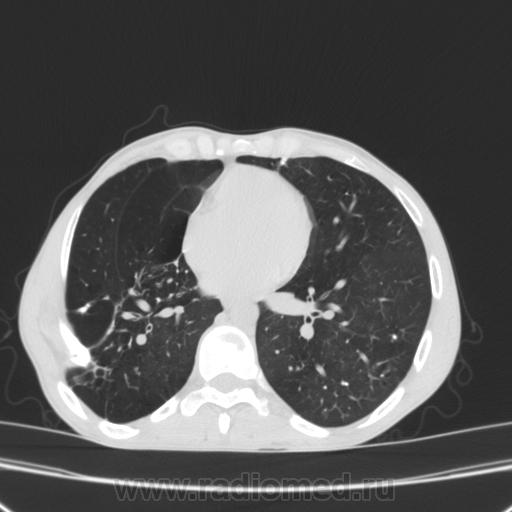

Состояние после торакопластики.

Молодой человек 30 лет, в 04 году выявлен фиброзно-кавернозный ТБ, в течение 12 месяцев лечился в стационаре, прооперирован-5реберная торакопластика справа, через 3 года переведен в 3ГДУ, в 10году снят с ДУ по излечению. Пришел провериться по ухудшению состояния. На КТ легких данных за рецидив ТБ, вроде нет. С " торакопластикой" был единственным пациентом на учете.

Состояние после правосторонней 5-реберной торакопластики по поводу ФКТ.Грубые остаточные изменения:поликистоз,буллезно-дистрофические изменения,плевропневмоцирроз правого легкого..Нет ли  мелкоочаговой диссеминации в обоих легких?Нужен Rархив.(ПТД).

Нет, это кальцинаты и более плотные уже. Архив только пленочный, 8 лет назад "цифры" не было. Можно и пленку перефотать...

Редко встречалось, а на КТ вижу впервые, спасибо за случай! На показанных изображениях отсевов не увидела.